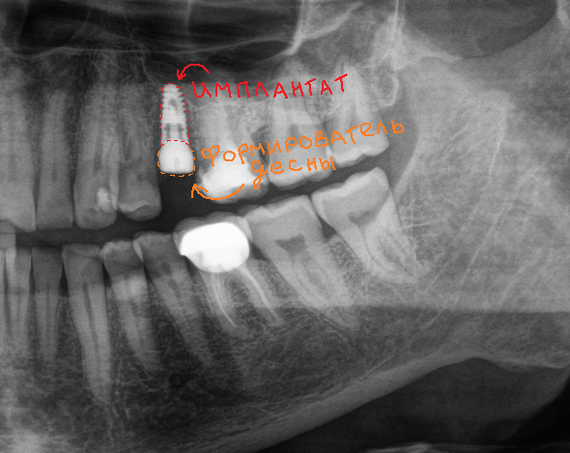

Я провел нежнейшее, атравматичное удаление зуба и установил имплантат с формирователем десны.

Формирователь десны — это что-то типа невысокого (в среднем 3мм. в высоту), металлического пенька, который немного торчит над уровнем десны, тем самым формирует ее контур перед установкой коронки. Выглядит он примерно так:

А так выглядит сам имплантат:

Серая часть — сам имплантат. Синяя часть — так называемый временный абатмент, на котором можно закрепить временную коронку, если имплантация сопровождается немедленной нагрузкой. В основном этот абатмент выступает в роли имплантодержателя. После того, как имплантат установлен, абатмент выкручивается, как конструктор — специальной отверткой, а на его место вкручивается заглушка. Она устанавливается в том случае, если невозможно сразу установить формирователь десны. Тогда имплантат и все составляющие его части находятся полностью под десной, а значит в полости рта после операции мы ничего не увидим. Ну, за исключением швов и… остальных зубов, если те еще остались. При таком раскладе формирователь устанавливается уже после того, как имплантат приживется.